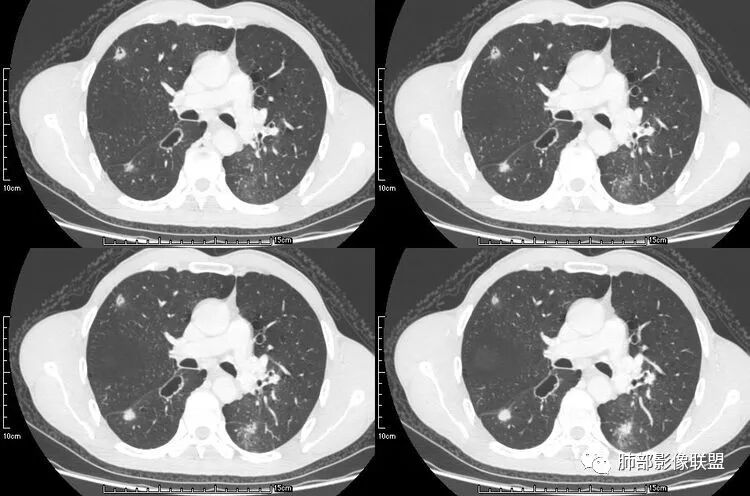

患者老年男性,咳嗽、咳痰、痰中带血伴胸闷2月余。长期大量吸烟史。查肝肾功能、血糖、血脂、心肌酶、电解质、血沉、C反应蛋白、抗“O”、类风湿因子、抗核抗体谱无明显异常。肿瘤标志物提示NSE、CYFRA21-1稍升高。胸部CT:肺气肿背景,左肺下叶后基底段不规则肿块影,见支气管截断,内见大片状低密度区及部分血管影,增强轻度强化,远端空洞形成。双肺多发不规则实性结节影、见毛刺、胸膜牵拉及血管集束,结节内见空洞形成,部分可见血管影,多位于胸膜下。双肺见多发肺大泡。综合考虑左下肺恶性病变并双肺转移。鳞癌或淋巴瘤可能。鉴别血管炎性病变及真菌感染。

肺腺癌伴双肺转移,双肺多发环形薄壁囊腔转移瘤;

来源于南京大学医学院鼓楼医院 周科峰